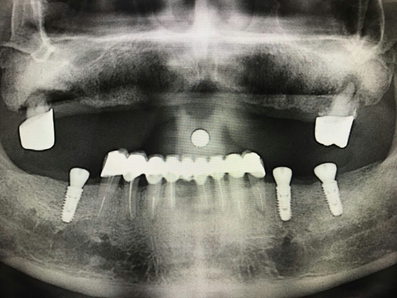

毛國斌種植病例——群討論分享